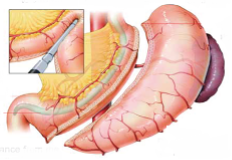

Επιμήκης γαστρεκτομή ή γαστρικό μανίκι ή «sleeve gastrectomy»

Χειρουργική επέμβαση εκλογής κατά την οποία αφαιρείται το 80%-85% του στομάχου κατά τον επιμήκη άξονά του, αφήνοντας ένα μακρόστενο λεπτό σωλήνα («μανίκι») που αντιστοιχεί στο 15-20% περίπου του στομάχου. Με αυτήν την τροποποίηση, ο ασθενής έχει αίσθημα πλήρωσης με μικρή ποσότητα τροφής, με αποτέλεσμα να χάνει βάρος.

Το τμήμα του στομάχου που αφαιρείται, περιέχει την ομάδα κυττάρων που παράγουν την ορμόνη γκρελίνη που ελέγχει την όρεξη καθώς και το αίσθημα της πείνας, έτσι οι ασθενείς χορταίνουν μετά τα μικρά τους γεύματα και αυτό έχει ως αποτέλεσμα την απώλεια κιλών αλλά και την διατήρηση στο επιθυμητό βάρος σε βάθος χρόνου.

Το μεγαλύτερο ποσοστό των ασθενών, μετά την επιμήκη γαστρεκτομή, παρουσιάζουν απώλεια βάρους που μπορεί να φτάσει έως και 80% του περιττού βάρους μέσα σε δώδεκα μήνες, και διατηρούν σταθερά τα αποτελέσματά τους για μεγάλο χρονικό διάστημα μετά και, εφόσον ακολουθούν τις διαιτητικές οδηγίες, δια βίου.

Επιμήκης γαστρεκτομή ή γαστρικό μανίκι ή «sleeve gastrectomy»

Χειρουργική επέμβαση εκλογής κατά την οποία αφαιρείται το 80%-85% του στομάχου κατά τον επιμήκη άξονά του, αφήνοντας ένα μακρόστενο λεπτό σωλήνα («μανίκι») που αντιστοιχεί στο 15-20% περίπου του στομάχου. Με αυτήν την τροποποίηση, ο ασθενής έχει αίσθημα πλήρωσης με μικρή ποσότητα τροφής, με αποτέλεσμα να χάνει βάρος.

Το τμήμα του στομάχου που αφαιρείται, περιέχει την ομάδα κυττάρων που παράγουν την ορμόνη γκρελίνη που ελέγχει την όρεξη καθώς και το αίσθημα της πείνας, έτσι οι ασθενείς χορταίνουν μετά τα μικρά τους γεύματα και αυτό έχει ως αποτέλεσμα την απώλεια κιλών αλλά και την διατήρηση στο επιθυμητό βάρος σε βάθος χρόνου.

Το μεγαλύτερο ποσοστό των ασθενών, μετά την επιμήκη γαστρεκτομή, παρουσιάζουν απώλεια βάρους που μπορεί να φτάσει έως και 80% του περιττού βάρους μέσα σε δώδεκα μήνες, και διατηρούν σταθερά τα αποτελέσματά τους για μεγάλο χρονικό διάστημα μετά και, εφόσον ακολουθούν τις διαιτητικές οδηγίες, δια βίου.